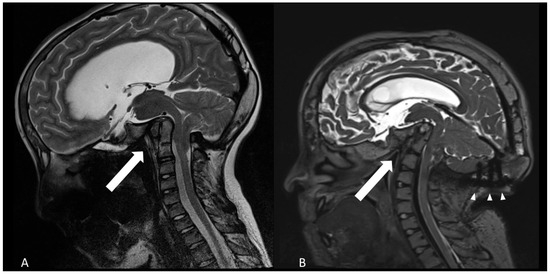

The patient’s clinical condition was significantly associated to basilar impression, as confirmed by the subsequent imaging studies (Figure 1). One year after VP-shunt insertion, the progressing basilar invagination had to be treated by decompression of the foramen magnum and fusion and decompression of C0–C2 (Figure 2). At age 13, the patient underwent posterior cranio-cervical surgery consisting of foramen magnum decompression in combination with C0–C2 decompression and occipito-cervical fixation spanning C0–C2. The decompression targeted the foramen magnum and the cranio-cervical junction to relieve brainstem compression. Fixation bridged the occiput to C2 to counteract progressive basilar invagination.

Compared with previous images, the radiological studies showed a continuing ascending tip of the dens axis with bending of the brainstem and folding of the angle between clivus and dens (Figure 1).

Figure 1. Progressive basilar invagination and flattening of the calvaria as shown by sagittal T2-weighted MRI. (A): age of 12 years (B): 18 years old. The arrows point to the angle between clivus and dens axis, diminishing from about 75° to 50°. Arrowheads show the occipital instrumentation.